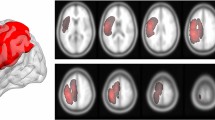

Tumor region of interest extraction

The Region of Interest(ROI) extraction methods are mostly the same as our previous study11. The tumor regions of each patient were manually segmented on T2-weighted images by two experienced neurosurgeons using MRIcron software (https://www.nitrc.org/projects/mricron). Abnormally hyperintense signals in T2-weighted images were determined as tumor areas. The cerebrospinal fluid region was carefully avoided. The final assessment was made by the radiologist. All tumor masks were registered to the MNI-152 standard brain template using the fMRIB software library (FSL; https://fsl.fmrib.ox.ac.uk/fsl/fslwiki/). An overlapping image of either left or right sided gliomas were then generated separately (Fig. 1).